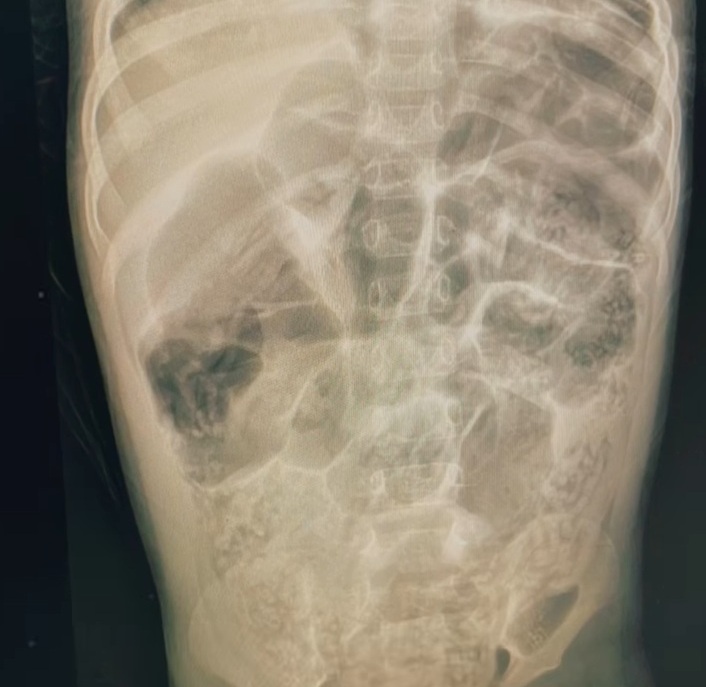

Jakarta: Baru-baru ini, ada kabar duka dari balita perempuan empat tahun di Sukabumi meninggal dunia akibat terdapat lebih dari satu kilogram cacing di tubuhnya yang terinfeksi hingga bagian organ intimnya. Cacing tersebut berjenis cacing gelang atau askariasis.

Menurut Ketua Tim Penanganan Keluhan RSUD R Syamsudin SH, Dokter Irfanugraha Triputra, infeksi cacing gelang ini sudah dikatakan parah. Cacing yang keluar dari hidung menandakan bahwa cacing sudah menjalar hingga saluran pernapasan atau saluran pencernaan bagian atas.

"Ini cenderung terlambat. Cacingnya sudah banyak sekali di dalam pencernaan dan sudah berukuran besar-besar," kata Irfanugraha kepada wartawan, dikutip dalam Liputan6, Rabu, 20 Agustus 2025.

Ascariasis ini terjadi ketika telur cacing gelang masuk ke dalam tubuh manusia. Cacing penyebab penyakit ini dapat menginfeksi paru-paru atau usus. Jika tidak dibasmi dengan pengobatan, cacing ini akan terus berkembang biak dan menginfeksi organ lain, seperti hati dan pankreas.

Cacing gelang sendiri pada beberapa kasus hidup di usus halus. Namun, larva cacing ini dapat menembus pembuluh darah dan menyebar ke organ lain. Telur yang masuk ke dalam tubuh akan menetas di usus dan menjadi larva. Selanjutnya, larva akan masuk ke paru-paru melalui aliran darah atau aliran getah bening.